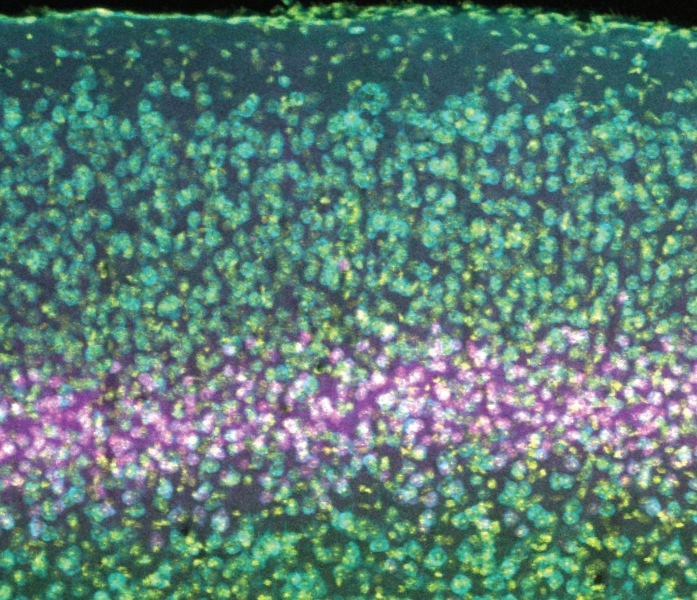

The visual cortex, where the brain processes visual input, is made like a stack of pancakes. In a new study, scientists sought to determine the role in several visual phenomena of a receptor on neurons in layer 4.

Photo: Bear Lab/Picower Institute

The cortex is built like a stack of pancakes, with distinct layers of cells serving different functions. Layer 4 is considered to be the primary “input layer” that receives relatively unprocessed information from each eye. Plasticity that is restricted to one eye has been assumed to occur at this early stage of cortical processing, before the information from the two eyes becomes mixed. However, while the evidence demonstrates that NMDA receptors in layer 4 neurons are indeed necessary for the degradation of vision in a deprived eye, they apparently play no role in how neural connections, or synapses, serving the uncompromised eye strengthen to compensate, and similarly don’t matter for the development of SRP. That’s even though NMDA receptors in visual cortex neurons have directly been shown to matter in these phenomena before, and layer 4 neurons are known to participate in these circuits via telltale changes in electrical activity.